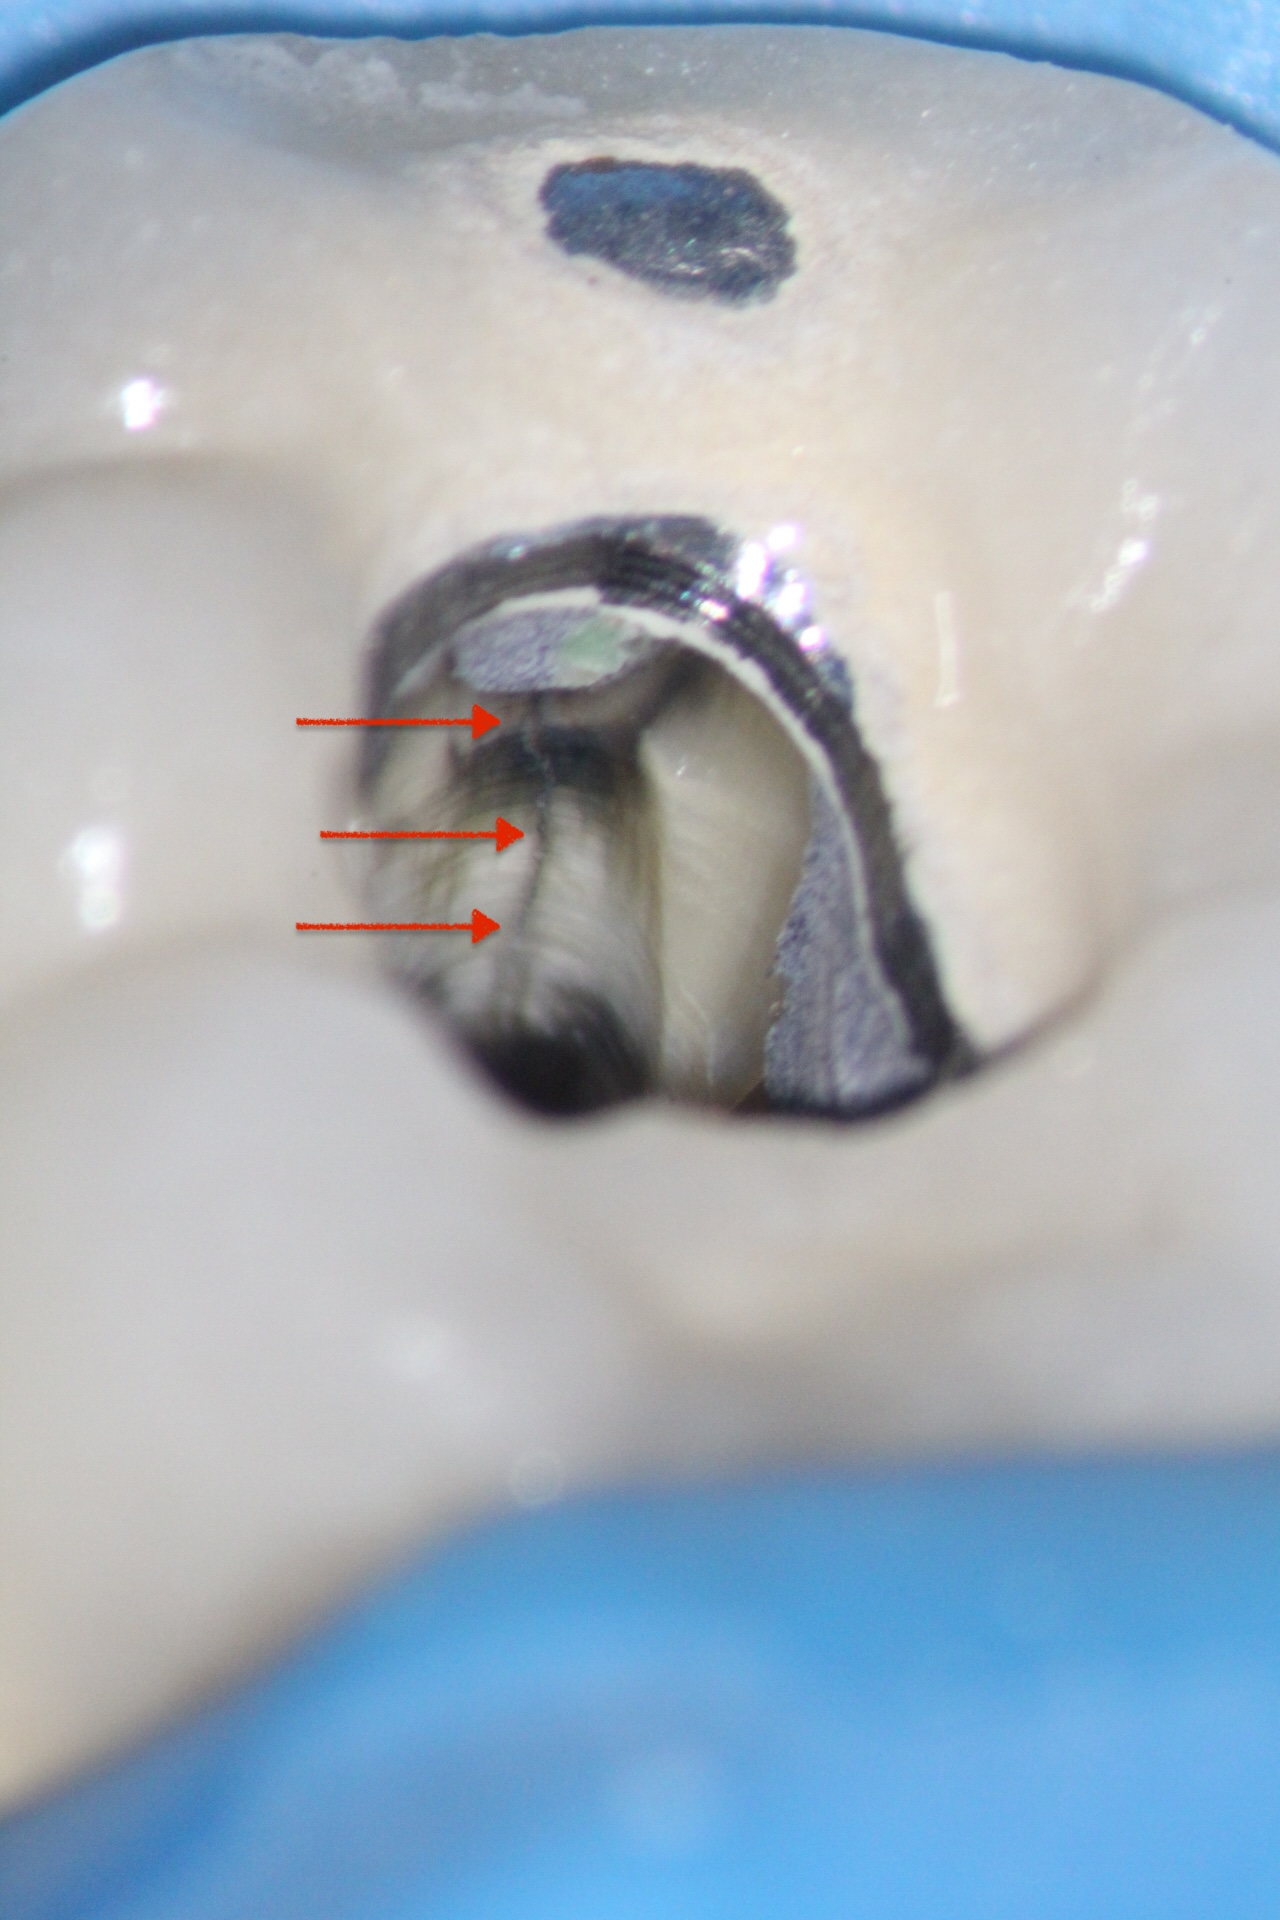

Resorption

Resorption is a condition where the tooth’s structure starts to break down, either from the inside out or from the outside in. It can be caused by trauma, inflammation, or other factors. Endodontic treatment for resorption involves removing the damaged tissue and reinforcing the tooth with materials that help prevent further damage. The aim is to save the tooth and maintain its functionality as much as possible.